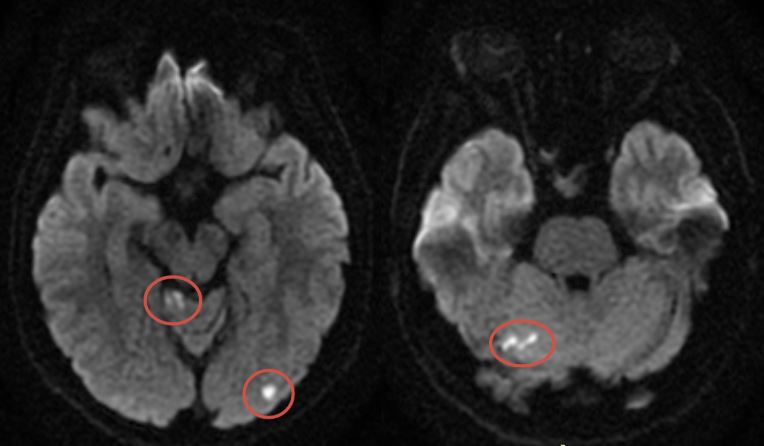

Ювенильный инсульт